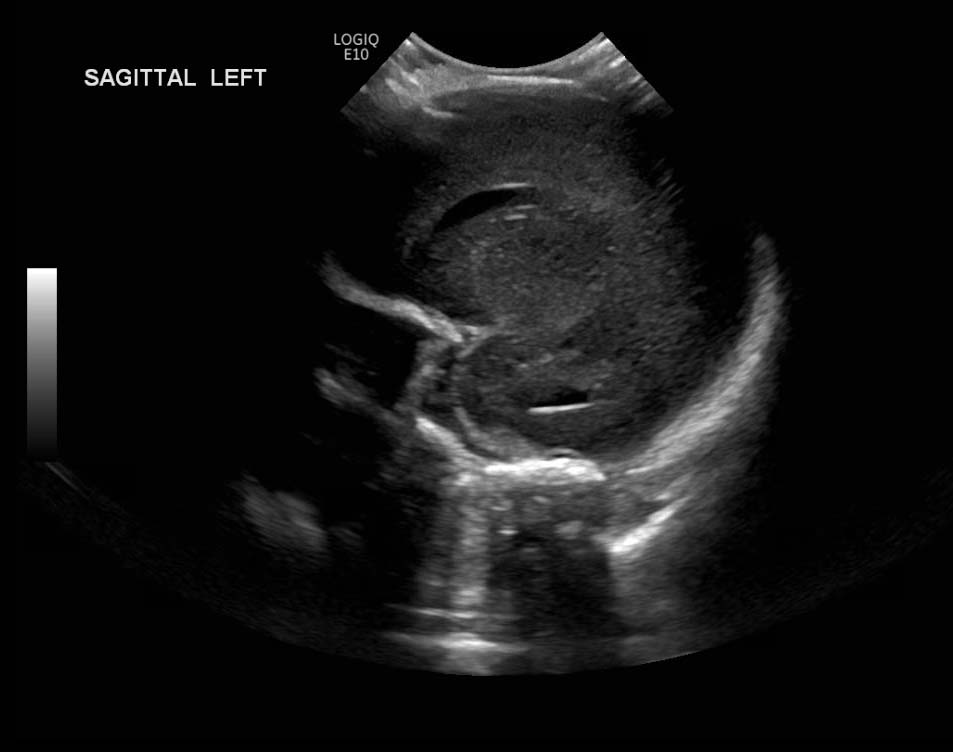

Age: 4 days (born at 24 weeks)

Sex: Male

Indication: Evaluate for germinal matrix hemorrhage

Grade 2 germinal matrix hemorrhage

Sample ReportLeft germinal matrix hemorrhage involving the caudothalamic groove and layering in the occipital horn of the left lateral ventricle without hydrocephalus (grade 2).

No abnormal brain parenchymal echogenicity or extra-axial collections.

Premature sulcation pattern.